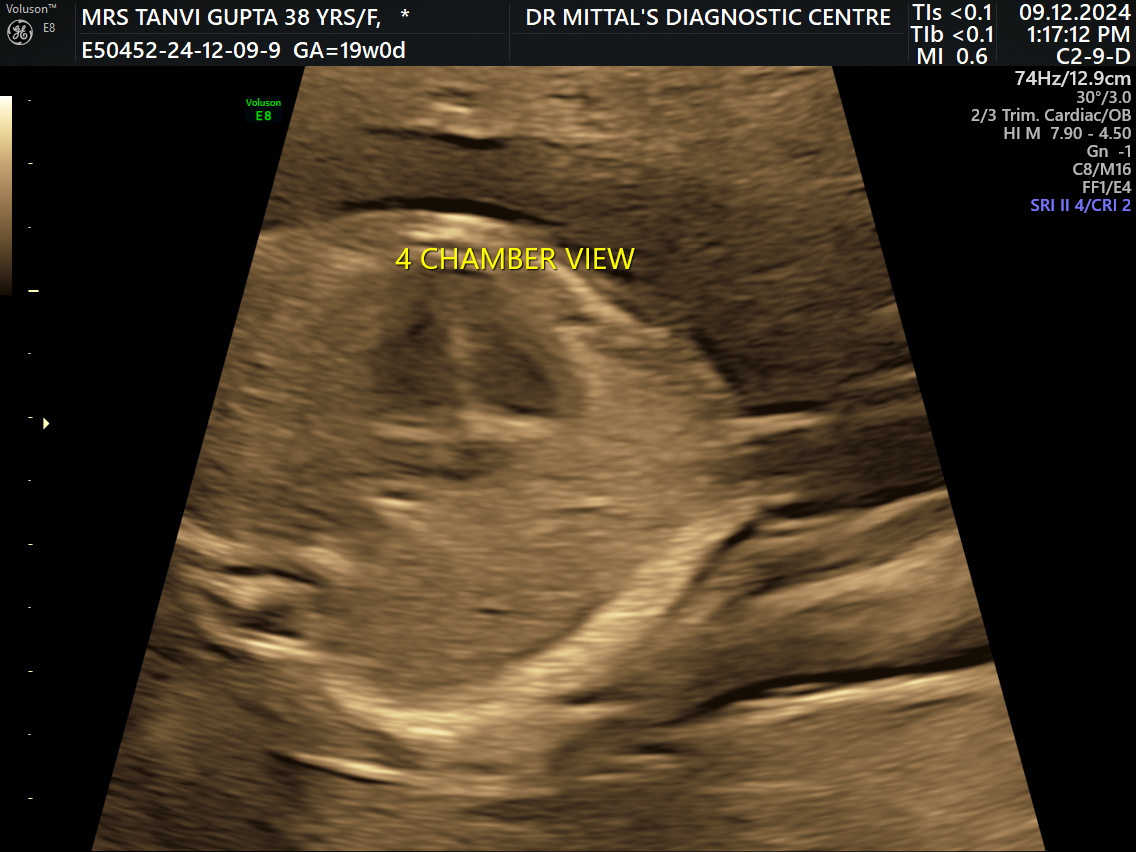

# FETAL ECHOCARDIOGRAPHY AVAILABLE # ROHINI # PITA...# FETAL ECHOCARDIOGRAPHY AVAILABLE # ROHINI # PITAMPURA A fetal echocardiogram, or fetal echo, is a non-invasive ultrasound imaging test that allows a doctor to examine the heart of an unborn baby. It's used to diagnose cardiac conditions in the fetus, which are one of the most common birth defects.